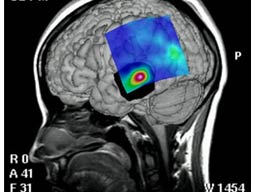

Kötü anıları silen beyin mekanizmasıAraştırmacılar kötü hatıralarla ilişkili travmatik hisleri söndüren beyin mekanizmasını tespit ettiler. Bu bulgu panik bozukluk tedavisine yönelik yeni ilaçların geliştirilmesine ön ayak olabilir.

Almanya, Muenster ve California Üniversitesi’nden araştırmacıların tespitine göre beyinde nöropeptid S isimli bir protein, amigdalanın içesindeki küçük bir nöron grubuna etki ederek, olumsuz hatıralara verilen travmatik yanıtları silmede etkili oluyor.

Yaptıkları testlerde, bilim adamları sıçanları olumsuz hatıraları tetikleyen durumlara maruz bıraktılar. Sonuç olarak, amigdala nöronlarındaki nöropeptid S reseptörleri bloke edildiğinde, kötü hatıralara verilen travmatik yanıtların daha uzun süre devam ettiği görüldü. Buna karşılık, sıçanlar bu reseptörleri aktive eden terkiplerle beslediğinde, travmatik yanıtlar daha hızlı bir şekilde ortadan kalktı.

Bir başka araştırma sonucuna göre, bu tarz negatif deneyimleri unutmak “yeni öğrenme”yle mümkün olabilmektedir. Mesela zarar verici sonuçlara yol açmaksızın, ilk deneyimin meydanan geldiği ortama yeniden maruz kalmak gibi. Reinscheid hatıraları söndürme olarak adlandırılan bu sürecin gerek insanlarda gerekse sıçan gibi laboratuvar hayvanlarında meydana geldiğini belirtiyor. Bu çalışmaya kadar, bilim adamları beyinde ürkütücü hatıraların söndürülmesinde rol oynayan spesifik nöron ve moleküllerden habersizlerdi.